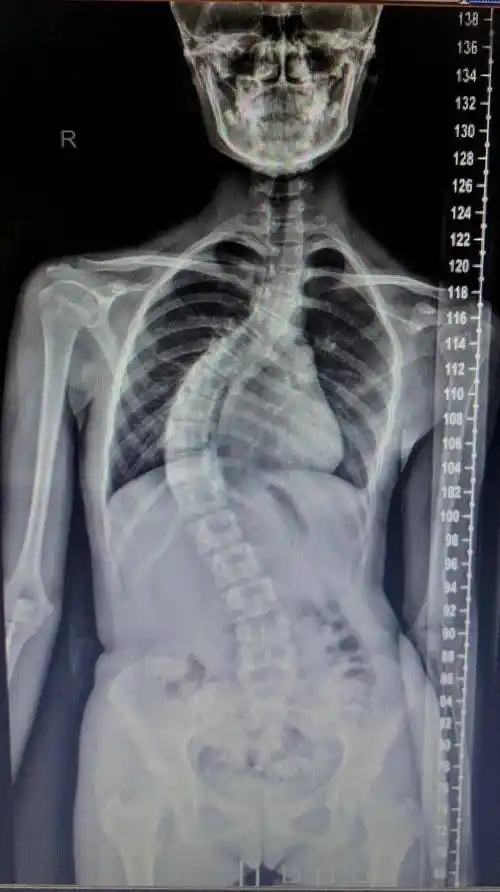

横断面的三维矫形,术前60°的主胸弯几乎获得完全矫正,术后剃刀背消失

剃刀背成青少年脊椎发育克星如何自查

非常明显的歪斜,甚至查体观察孩子的背部已经有非常明显的"剃刀背"

什么是"剃刀背"?